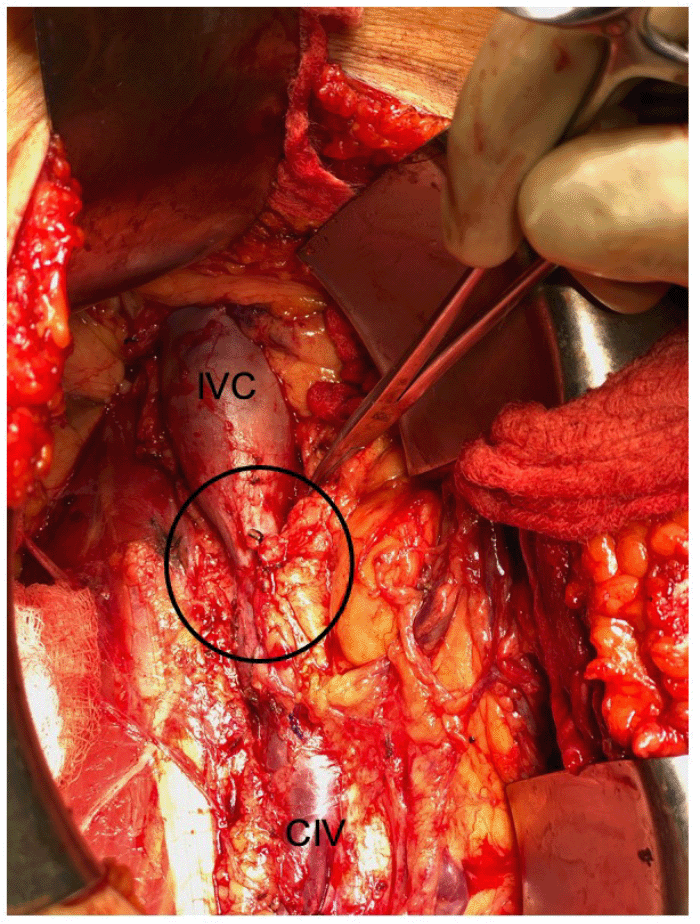

The patient is a 69-year-old male with a history of severe chronic obstructive pulmonary disorder (COPD) requiring bilateral lung transplants and end-stage renal disease secondary to resulting calcineurin toxicity, who presented to our institution for deceased-donor kidney transplantation. He also had a history of deep vein thrombosis and pulmonary embolism (DVT/PE) requiring remote infrarenal IVC ligation to prevent thrombosis propagation after developing intraabdominal bleeding while on anticoagulation. A computed tomography (CT) scan of the abdomen and pelvis was obtained on his arrival at our facility to delineate his abdominal venous outflow better and assist with surgical planning (Figure 1).

Figure 1. Location of Infrarenal IVC Ligation (arrow). Published with Permission

The right-sided deceased donor kidney was then inspected. The donor renal vein had been procured along with 2 cm proximal and 8 cm distal donor IVC. The patient was taken to the operating room for a planned renal transplant in the right iliac fossa, using recipient IVC just proximal to his obstruction as the site for venous drainage of the allograft. An inverted donor IVC conduit was created to maximize the proximity of the allograft to the right iliac artery and bladder. The donor renal vein was divided from the donor IVC, which was then rotated 180º. The donor renal vein was re-implanted at its original orifice, now at the inferior aspect of the IVC, creating a conduit from the renal hilum running superiorly. The inferior IVC cuff was then oversewn. A right lower quadrant curvilinear incision and a right retroperitoneal dissection were performed (Figure 2).